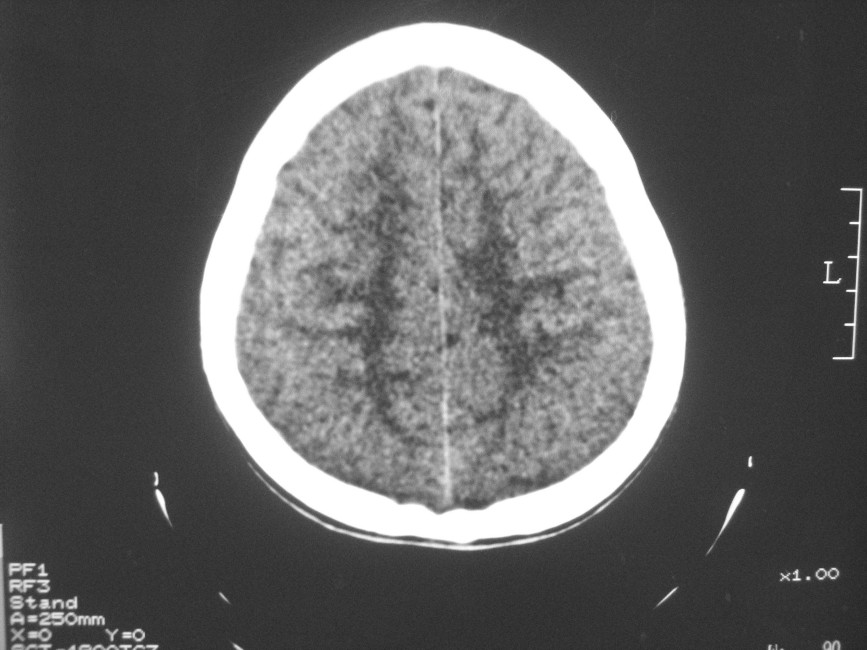

以下是引用zzyy在2008-6-16 10:13:00的发言:[br]两侧脑白质呈对称性密度减低,病儿有发热及脑膜刺激征。考虑急性病毒性脑炎。